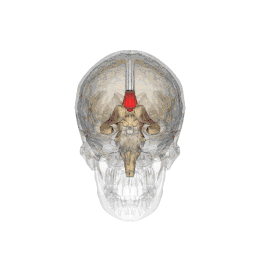

Le corps calleux (ou corpus callosum) est une commissure (moyen d'union entre deux parties) transversale du cerveau présente chez les mammifères placentaires[1]. C’est un faisceau d'axones (fibre nerveuse qui correspond au prolongement long, mince et cylindrique du corps cellulaire d'un neurone) interconnectant les deux hémisphères cérébraux. C'est la plus importante commissure du cerveau, car elle relie les huit lobes du cerveau entre eux (lobes frontaux, temporaux, pariétaux et occipitaux gauche et droit). Le corps calleux assure donc le transfert d'informations entre les deux hémisphères et ainsi leur coordination. Les autres commissures sont le fornix, le cingulum et la commissure blanche antérieure.

D’avant en arrière, on peut délimiter trois structures :

- le « genou » et le tiers antérieur du corps calleux (bec ou rostrum) sont ainsi formés par les fibres qui unissent les deux cortex (lobes) frontaux ;

- le tiers moyen (ou tronc) est formé par les fibres qui unissent les cortex pariétaux et temporaux ;

- la partie la plus postérieure, (bourrelet ou splenium), est formé par les fibres qui unissent les deux cortex occipitaux.